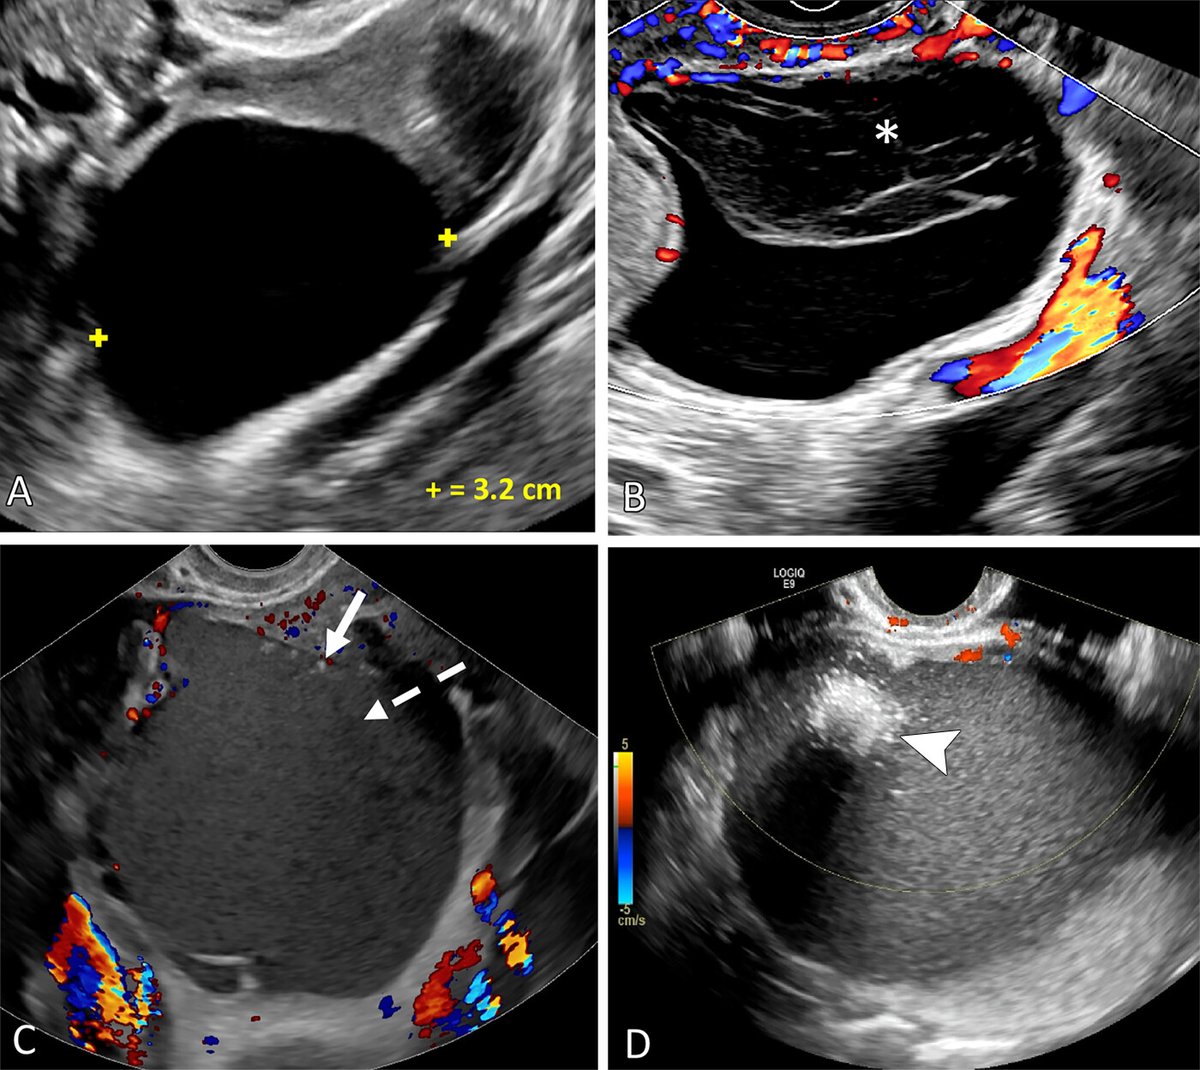

Recognize the MRI features of placenta accreta spectrum disorders, which are increasing in incidence with the rising rate of cesarean deliveries. bit.ly/3VK1gsE @VUMCradiology Krupa Patel-Lippmann Virginia Planz Catie Phillips, MD @moshirimd @VUMC_obgyn

Recognize the MRI features of placenta accreta spectrum disorders, which are increasing in incidence with the rising rate of cesarean deliveries. bit.ly/3VK1gsE @VUMCradiology <a href="/KPatelLippmann/">Krupa Patel-Lippmann</a> <a href="/VPlanz/">Virginia Planz</a> <a href="/CatiePhillips1/">Catie Phillips, MD</a> @moshirimd @VUMC_obgyn

Recent awesomeness from the #BodySection @VUMCradiology! Check out this RadioGraphics update & review article from Society of Abdominal Radiology | SAR⭐️s Krupa Patel-Lippmann, Virginia Planz, @moshirimd, Catie Phillips, MD, & MFM⭐️Lisa Zuckerwise & our former fellow Dr. Ohlendorf! pubs.rsna.org/doi/10.1148/rg…

Recent awesomeness from the #BodySection @VUMCradiology! Check out this <a href="/RadioGraphics/">RadioGraphics</a> update &amp; review article from <a href="/SocietyAbdRad/">Society of Abdominal Radiology | SAR</a>⭐️s <a href="/KPatelLippmann/">Krupa Patel-Lippmann</a>, <a href="/VPlanz/">Virginia Planz</a>, @moshirimd, <a href="/CatiePhillips1/">Catie Phillips, MD</a>, &amp; MFM⭐️<a href="/LCzuckerwiseMD/">Lisa Zuckerwise</a> &amp; our former fellow Dr. Ohlendorf! pubs.rsna.org/doi/10.1148/rg…